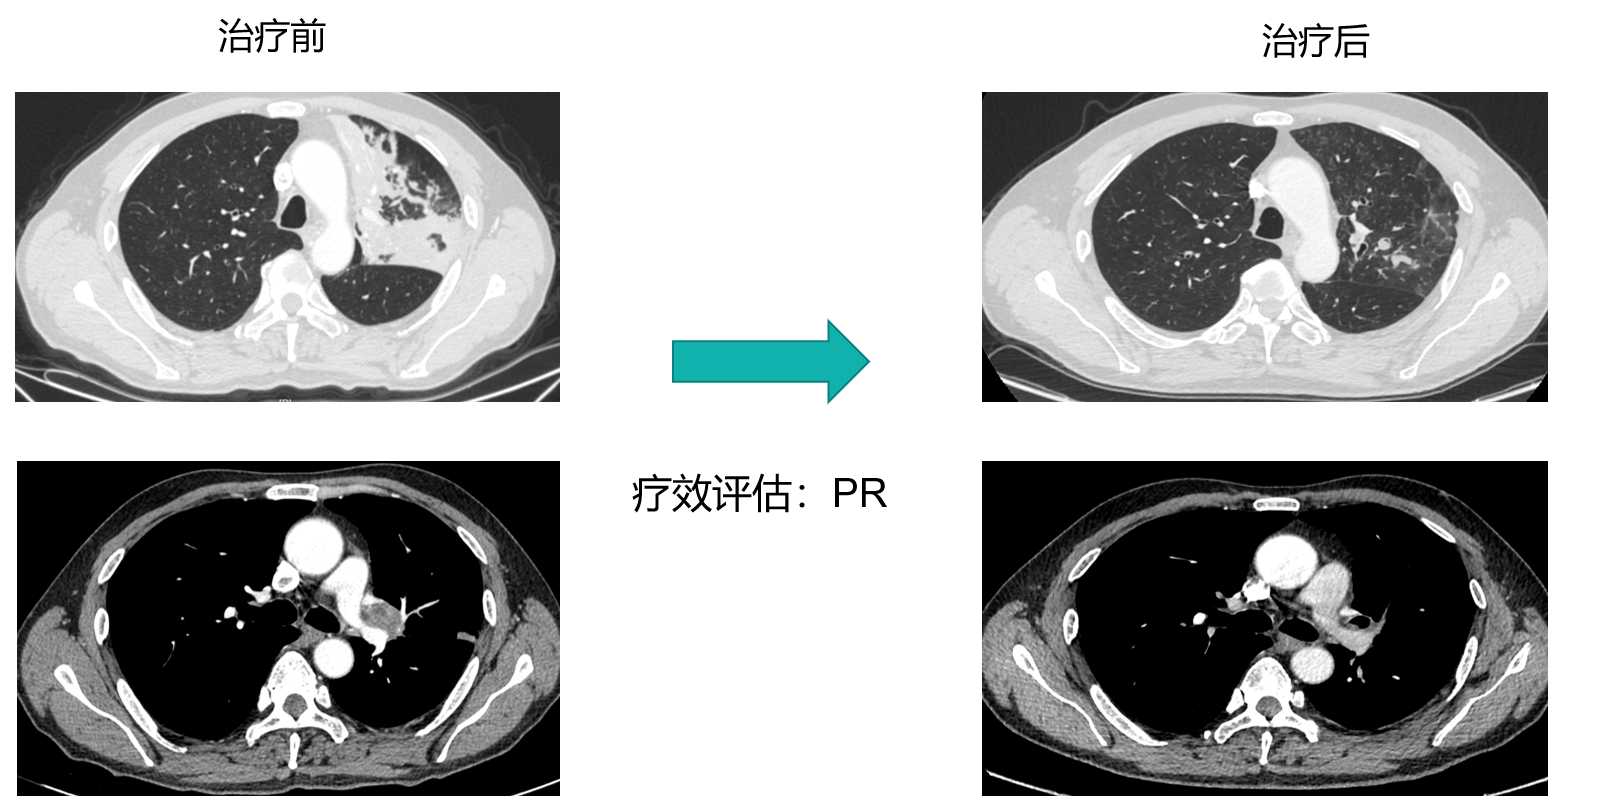

影像学评估: 治疗后复查胸部CT(2022/1/6)显示左肺门占位较前范围缩小(1.2x1cm),左肺门淋巴结缩小,炎性改变明显好转。疗效评估为部分缓解(PR)。

手术实施: 2022年1月12日,患者在全麻下行胸腔镜下左肺上叶切除术(袖状切除)+淋巴结清扫术。手术过程顺利,未发生治疗相关不良反应,手术难度因肿瘤显著退缩而降低。

术后病理:左上叶袖形切除标本。镜下见纤维组织增生、伴淋巴细胞及浆细胞浸润,结合病史,符合治疗后改变,未见肿瘤残留,瘤床大小1.5x0.7x0.7(cm)。支气管上、下切端阴性。淋巴结(4L、5、6、7、8、9、10、11)共8组慢性炎,未见肿瘤。疗效评估pCR(病理学完全缓解)。

沈岚教授:本例患者为54岁男性,初诊即为IIIA期(N2)中央型肺鳞癌,属于局部晚期肺癌,治疗难度较大。MDT讨论制定了基于免疫联合化疗的新辅助治疗策略。患者在接受3周期纳武利尤单抗联合含铂双药化疗后,影像学显示肿瘤显著缩小,达到PR。后顺利实施了肺叶袖状切除术,无术中及术后不良并发症,最大程度保留了肺功能。术后病理提示原发灶及清扫淋巴结均无肿瘤残留,达到了pCR。这一结果不仅验证了该方案的卓越疗效、极大提高了生活质量,预示着良好的长期生存。